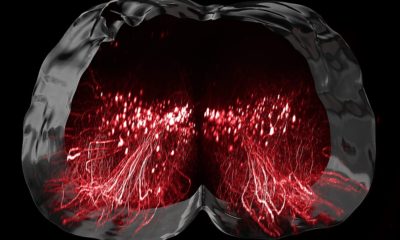

Deux types d’implants électroniques ont été nécessaires. "L'un est installé au-dessus de la région du cerveau qui est responsable des mouvements des jambes", explique la neurochirurgienne Jocelyne Bloch, également professeure au CHUV, à l’UNIL et à l’EPFL. Ce dispositif comportant 64 électrodes permet de décoder les signaux électriques générés par le cerveau lorsque le sujet pense à marcher.

Parallèlement, un neurostimulateur connecté à seize électrodes a été positionné sur la région de la moelle épinière qui contrôle le mouvement des jambes. Grâce à des algorithmes basés sur des méthodes d’intelligence artificielle adaptatives, les intentions de mouvement sont décodées en temps réel.

Ces intentions sont ensuite converties en séquences de stimulation électrique de la moelle épinière, qui à leur tour activent les muscles des jambes pour réaliser le mouvement désiré. Ce pont numérique opère en mode sans fil, permettant ainsi au patient de se déplacer en toute autonomie.